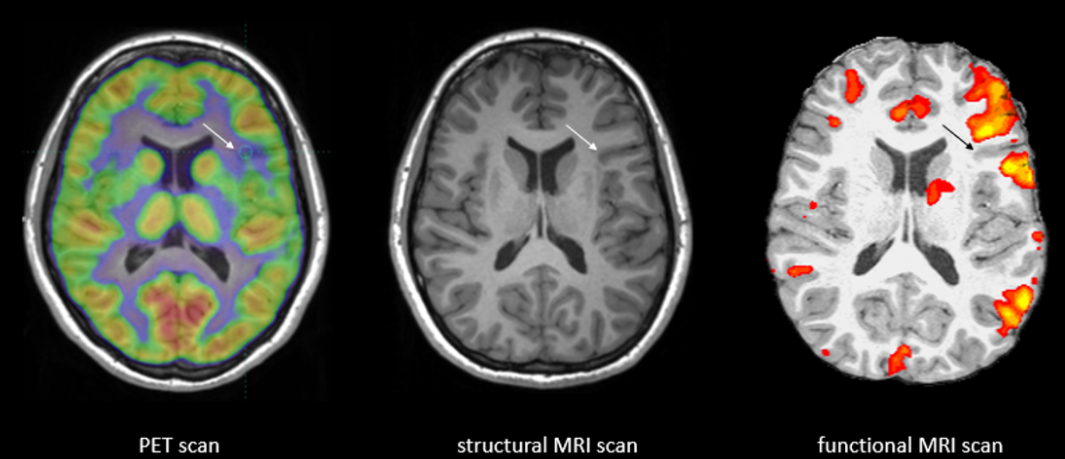

56 Top Photos Cat Scan Vs Mri Vs Pet Scan : Plos One Hybrid Fdg Pet Mri Vs Fdg Pet And Ct In Patients With Suspected Dementia A Comparison Of Diagnostic Yield And Propagated Influence On Clinical Diagnosis And Patient Management. .scan and an mri scan however, when i was first diagnosed, i was sent for a pet scan as supposedly, these show more detail. There is no radiation hazard risk for the patients undergoing an mri scan. What is the difference between mri and pet scans? Ct scans and mri scans are two medical imaging methods that create detailed images of internal body parts, including bones, joints, and organs. Mike shows you how they are both used and sheds light on what an mri, cat scan (ct scan), and a pet scan is.

An mri is suited for examining soft tissue in ligament and tendon injuries, spinal cord injuries, brain tumors, etc. How do mri, pet and cat scans work? Difference between cat scan and mri электронный ресурс. Mike shows you how they are both used and sheds light on what an mri, cat scan (ct scan), and a pet scan is. Positron emission tomography (pet) scans use a special dye that contains radioactive tracers to identify how well your organs and other tissue inside your body are functioning.

Mri Vs Pet Scan Which One You Should Get And Why from post.healthline.com Pet scans (positron emission tomography scans) are often done in conjunction with ct scans (computerized tomography scans) or mri scans (magnetic resonance imaging scans). Diffen › health › diagnostics. Positron emission tomography (pet) imaging scans use a radioactive tracer to check for signs of cancer, heart disease and brain disorders. Ct scan costs range from $1,200 to $3,200; Primarily a medical imaging technique most commonly used in. A pet scan allows physicians to measure the body's abnormal molecular cell activity mri: A ct scan (or cat scan) is finest matched for diagnosing bone injuries, identifying lung and chest difficulties, and sensing cancers. Mike shows you how they are both used and sheds light on what an mri, cat scan (ct scan), and a pet scan is.

While ct and mri scans show images of your body's internal organs and tissues.

Computed axial tomography (cat or ct) was introduced in. Mike shows you how they are both used and sheds light on what an mri, cat scan (ct scan), and a pet scan is. At health images, we use the latest ct scan technology to get patients in and out of the. Some hospitals now use a hybrid pet/mri scan. A ct scan (or cat scan) is finest matched for diagnosing bone injuries, identifying lung and chest difficulties, and sensing cancers. Pet scans (positron emission tomography scans) are often done in conjunction with ct scans (computerized tomography scans) or mri scans (magnetic resonance imaging scans). The person lies on a table that moves through a scanning ring our doctors use advanced imaging tests, such as ct scans, mris, and pet scans, to help detect and diagnose disease, make appropriate treatment. .scan and an mri scan however, when i was first diagnosed, i was sent for a pet scan as supposedly, these show more detail. Image slices that ct scans produce can be 2 or 3 dimensional and can reveal abnormal structures or help the physician plan and moni. What is the main difference between ct scan and mri and which one is best. Ct scan costs range from $1,200 to $3,200; How does a ct scan (cat scan) work? Some patients find an mri claustrophobic.

Image slices that ct scans produce can be 2 or 3 dimensional and can reveal abnormal structures or help the physician plan and moni. The person lies on a table that moves through a scanning ring our doctors use advanced imaging tests, such as ct scans, mris, and pet scans, to help detect and diagnose disease, make appropriate treatment. Diffen › health › diagnostics. .scan and an mri scan however, when i was first diagnosed, i was sent for a pet scan as supposedly, these show more detail. Pet scans cost $3,000 to $6,000; Positron emission tomography (pet) scans use a special dye that contains radioactive tracers to identify how well your organs and other tissue inside your body are functioning. There is no radiation hazard risk for the patients undergoing an mri scan. Ct was developed independently by a british engineer named sir godfrey hounsfield and dr. Question 🤔🤔fmri vs pet scan? Ct scan costs range from $1,200 to $3,200; Ct scans and mri scans scan similar areas of the body to diagnose injuries and internal pain, but the technology is different. Ct scans are more common and less expensive, but mri. I believe a ct scan along with an mri should be enough for your doctors to determine that you are in good shape.